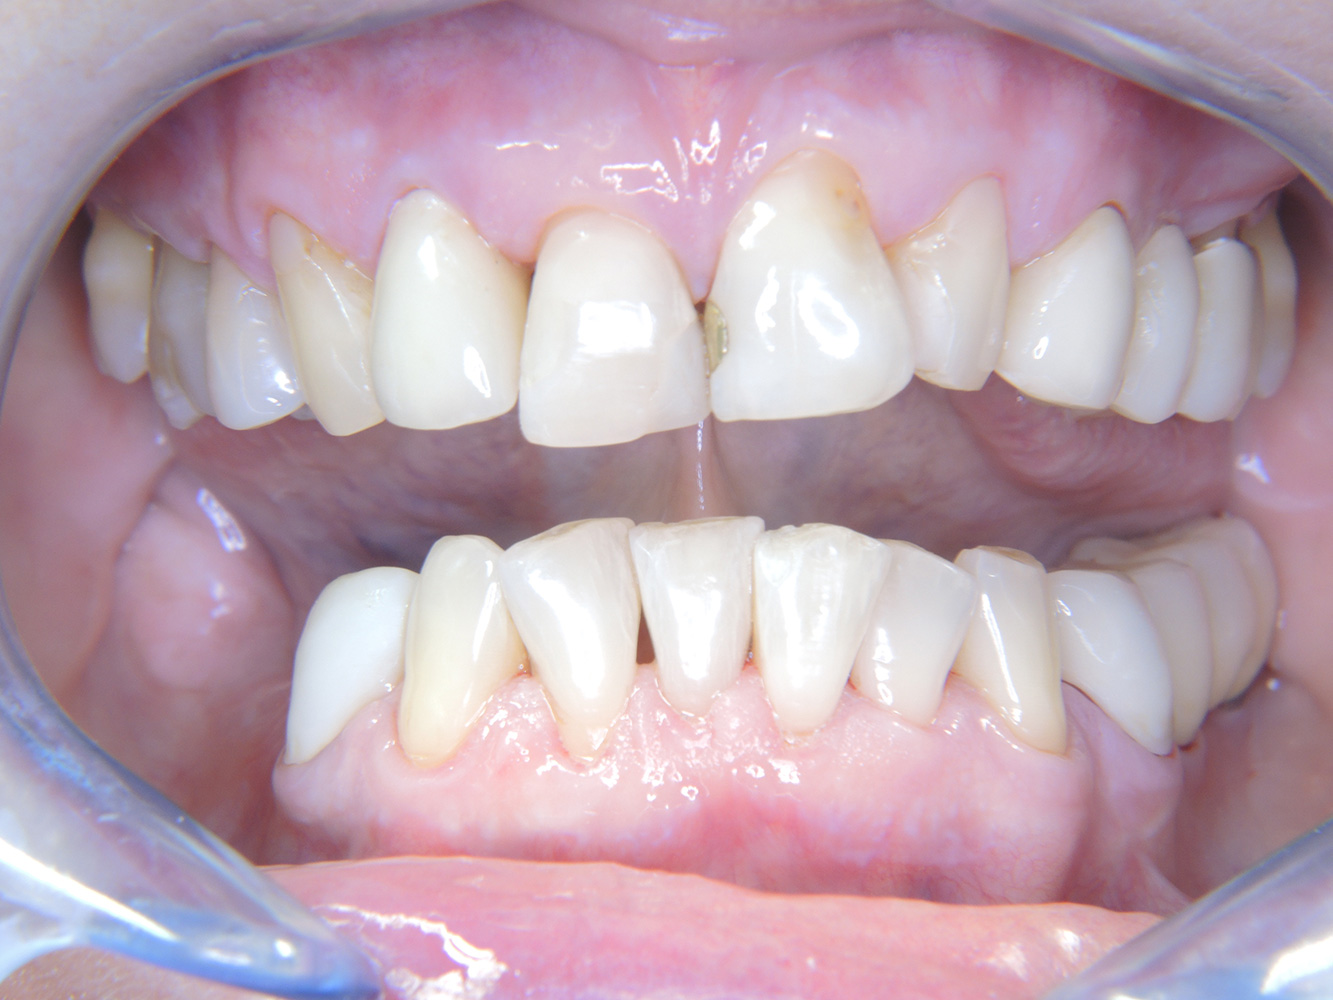

The healthy patient with

early periodontal disease*

The 68-year-old patient has no general health conditions and is not taking any medication that may be relevant to her oral health, and her lifestyle does not pose any particular risk. The patient has two dental implants (3rd quadrant, for five years) and a previous case of periodontal disease (stage IV, grade B periodontitis) with tooth loss. Currently the periodontal conditions are stable. However, periodontitis significantly increases the biological complications of implantations and there is a risk of implant loss (21). Four recommendations can be determined for the prophylaxis session.

As the patient does not have any particular risk factors with specific dental implications, the requirements determined from her current state of oral health are crucial. Here, it is recommended that a thorough assessment of periodontal condition be carried out once a year. This will ensure that any potential progression of the previous periodontal disease or development of peri-implantitis can be responded to in good time.

Despite the stable conditions, it is also crucial for the instructive/motivational discussion to be conducted with this patient. Particular attention should be paid to teaching the patient how to care for the implants correctly. Here in particular, good at-home maintenance can have a significant impact on the long-term stability of oral and implant health.

Because the patient has implants and a history of periodontal disease, she is at risk of developing peri-implantitis. It is therefore recommended that she attend a recall session every three to four months.